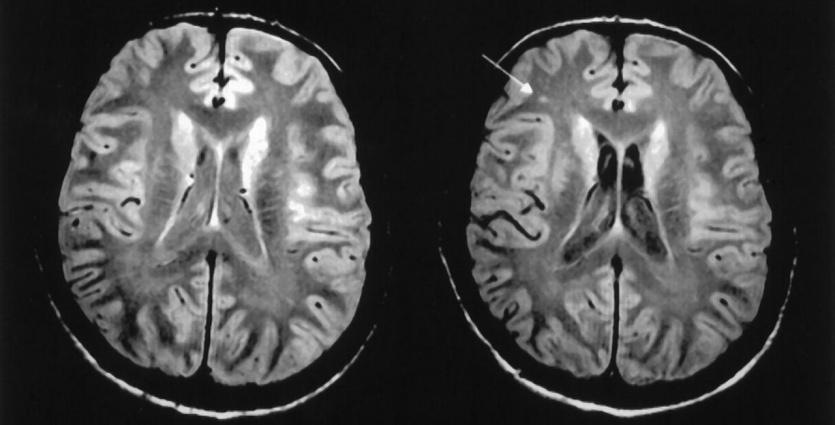

المادة البيضاء في الدماغ

المادة بالبيضاء هي عبارة عن نسيج يغطي الأجزاء العميقة من الدماغ، يتكون من ألياف عصبية تسمى المحاور العصبية التي تربط ما بين الخلايا العصبية، تغطيها مادة دهنية تسمى غمد الميالين. (هو الذي يعطي المادة البيضاء لونها.)

تشكل المادة البيضاء حوالي نصف الدماغ، بينما تشكل المادة الرمادية (هو نسيج موجود على سطح الدماغ تعتبر القشرة الدماغية يحتوي على أجسام الخلايا العصبية، والتي تعطي المادة الرمادية لونها) النصف الاخر.

مرض المادة البيضاء

هو عبارة عن اضطراب يحدث نتيجة تاكل الأنسجة في الجزء العميق من الدماغ وهو التغير في المادة البيضاء.